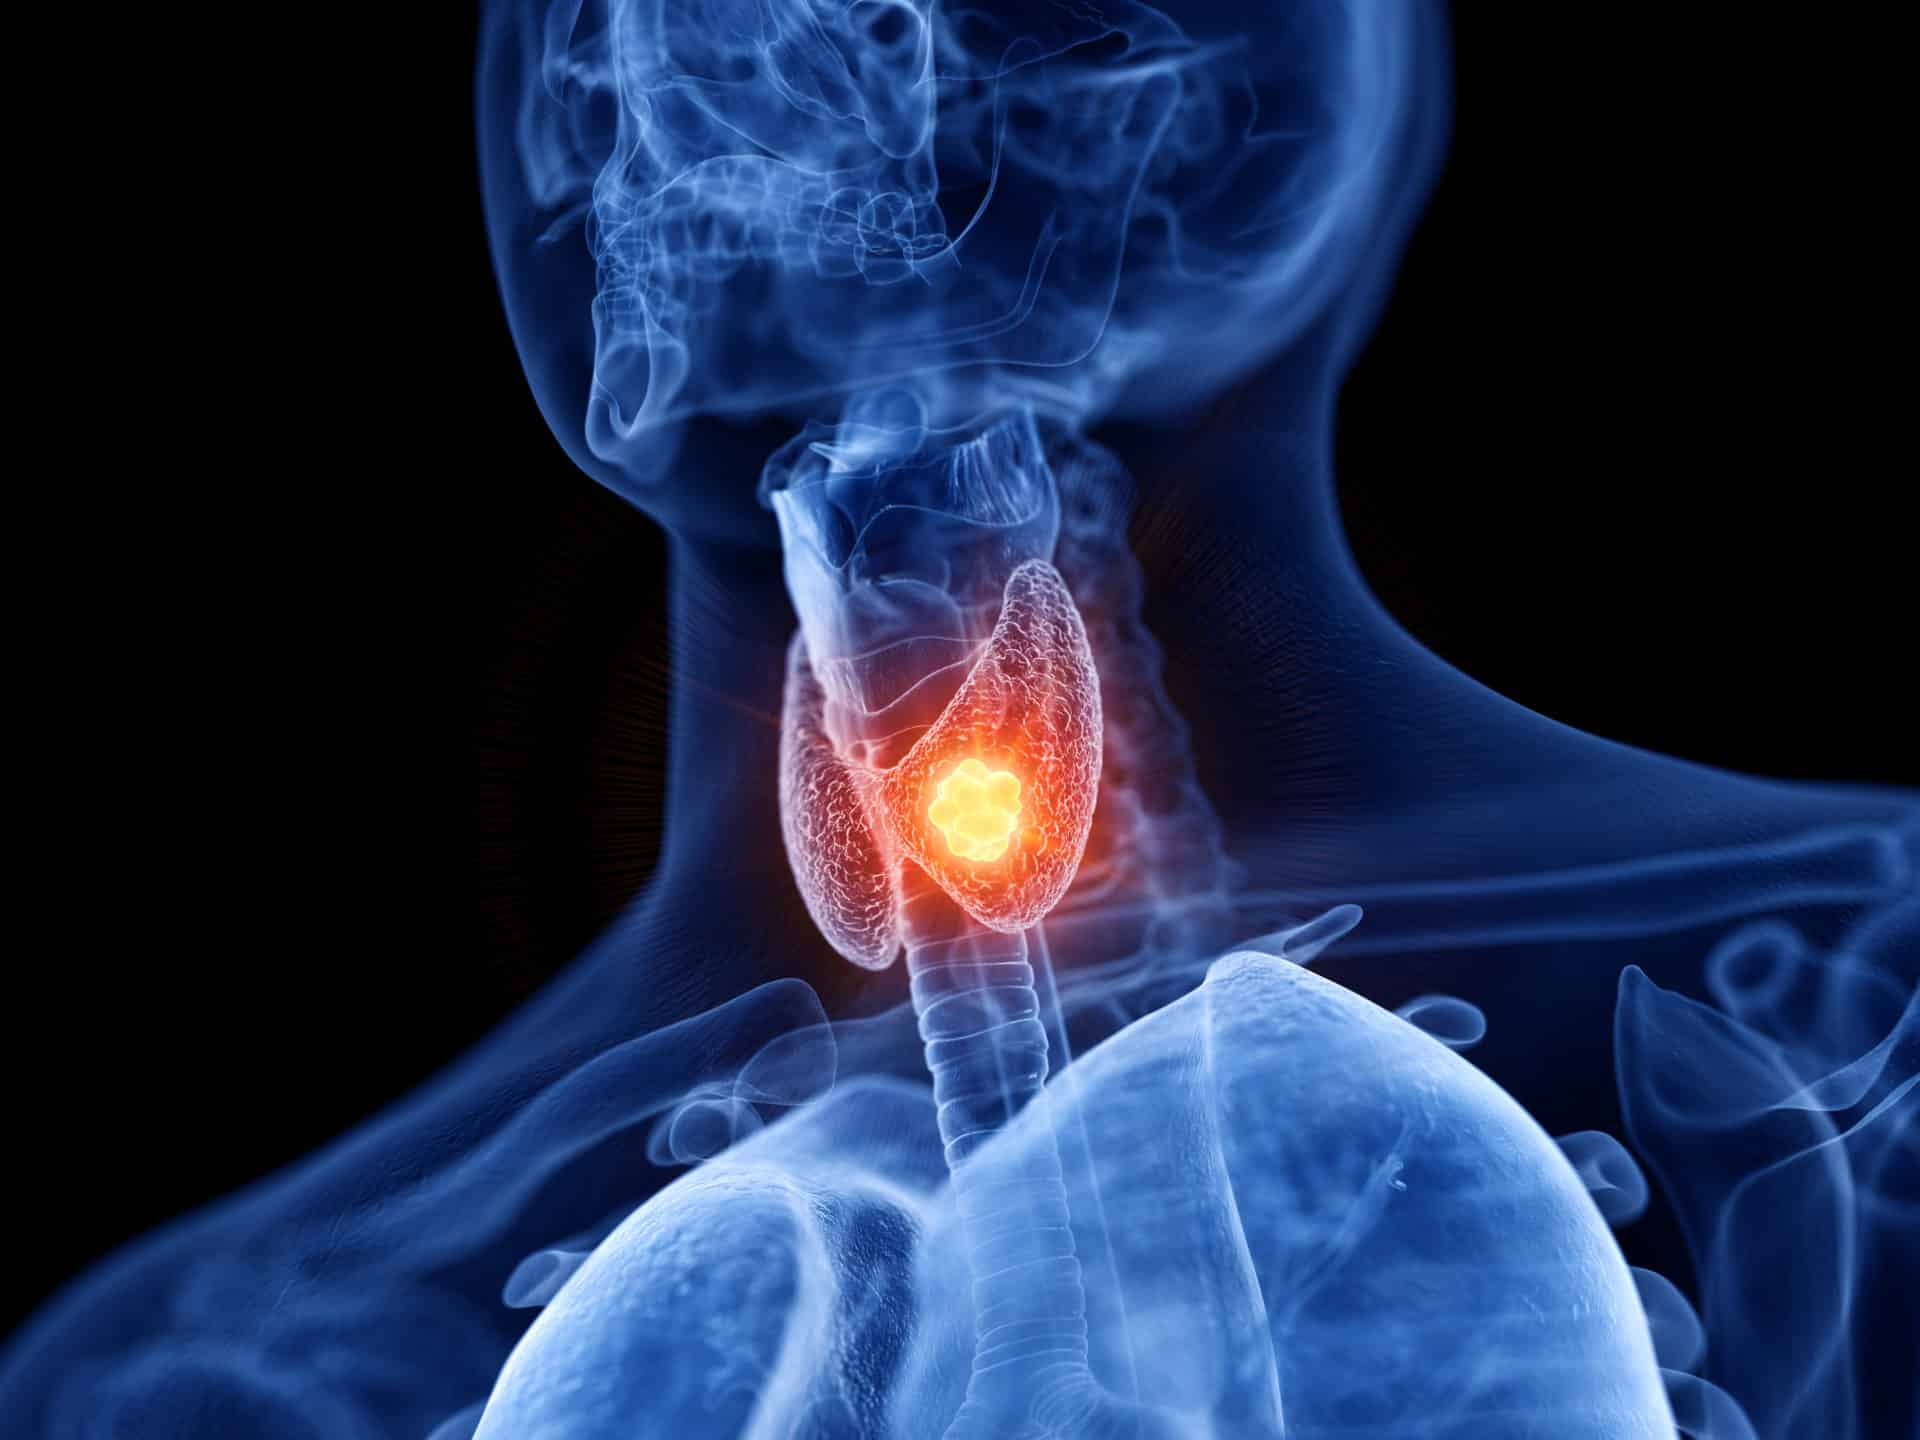

العقيدات الدرقية | أسباب وأعراض وعلاج حالة الـ Thyroid nodules

العقيدات الدرقية عبارة عن غدد على شكل فراشة يبلغ طولها حوالي بوصتين وتقع في قاعدة عنقك، حيث تلعب هذه الغدة دوراً كبيراً في جسمك، حيث إنها مسؤولة عن إفراز الهرمونات التي تتحكم في عملية التمثيل الغذائي بالطريقة التي يستخدم بها جسمك الطاقة.

كذلك، تنظم الهرمونات التي تفرزها الغدة الدرقية مجموعة من وظائف الجسم بما في ذلك معدل ضربات القلب والتنفس ودرجة حرارة الجسم ووظيفة الجهاز العصبي وغير ذلك الكثير، وبالتالي، عندما يكون هناك شيء خاطئ في العقيدات الدرقية، يمكن أن يتسبب ذلك في إبعاد كل أجهزة الجسم ناهيك عن مزاجك.